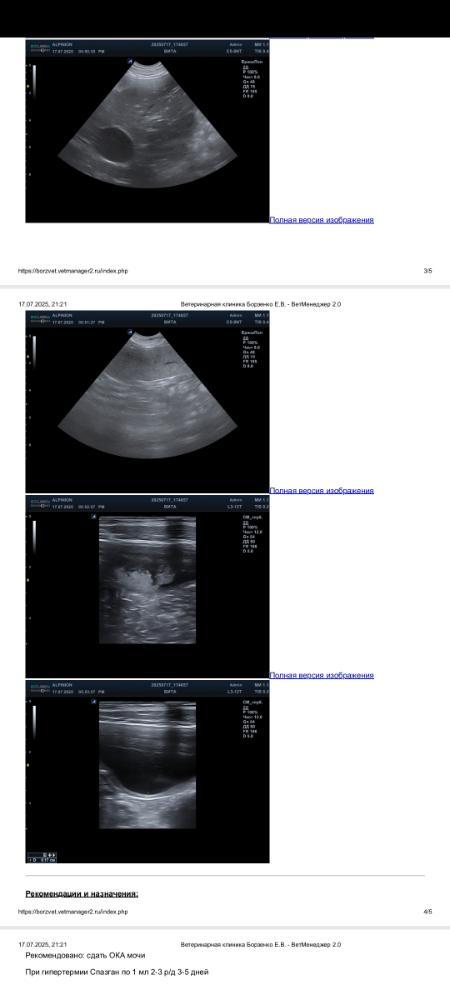

Отчет по узи Виты

Screenshot_20250717_212519_com.huawei_docs.jpg.93e5ac74a0ed2fbaf03cccd0e837a944.jpg

Screenshot_20250717_212527_com.huawei_docs.jpg.04096fcbcb65538b2ab66643a3ddf317.jpg

Screenshot_20250717_212536_com.huawei_docs.jpg.522b5d1efe21e0a7e32ab80ac4e85473.jpg

Screenshot_20250717_212545_com.huawei_docs.jpg.a7e95bbe4921de97e29617162daaccc8.jpg

IMG_20250717_200923.jpg.90f96118e1606537cfcc19872f954792.jpg

Чтобы пояснить мое восхищение, собаке 4.5 года.

Терапия на данный момент от такая. Пагля-это пагля -3, где 50 мг фенобарбитала в каждой таблетке

То есть у собаки более 11 мг на кило каждый день.IMG_20250717_204016.jpg.2a6041f717f07df9828eeb11042a85b7.jpg

А еще у Виты кеппры дофига и габапентина. Несколько лет на терапии, практически вровень с Эшкой по возрасту. И показания по узи-космонавт. Мы и кровь поэтому не стали сдавать. Смысла ноль. Ее все обсмотрела врач. Даже стоя.